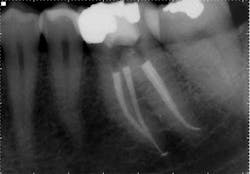

While mandibular incisors are my least favorite teeth to treat, the premolar teeth also provide significant reason for concern as they have highly variable anatomy. The maxillary first and second premolars will have one, two, or three roots and canals. (Figure 3) Maxillary premolar teeth have the smallest mean apical dimension at the apex (11) and the most variable anatomy, with exception of third molars. (12,17) The roots are often very thin, and a bulbous clinical crown may have significant taper to a thin root in the mesial-distal dimension that is broad in the facial-lingual dimension. It is not uncommon to see mesial-distal fractures in maxillary first or second premolars. Maxillary second premolars may have more curvature in the apical portion of the root when the sinus is close to the root ends. (Figure 4)

following root canal treatment in teeth Nos. 4 and 5. An angled

radiograph indicated a high probability for an untreated canal in

tooth No. 4 and as a result, this tooth was retreated.

increased concern about the anatomy in tooth No. 5. This tooth

was subsequently retreated due to persistent symptoms.

were present in both Nos. 4 and 5 following the initial root

canal treatment.